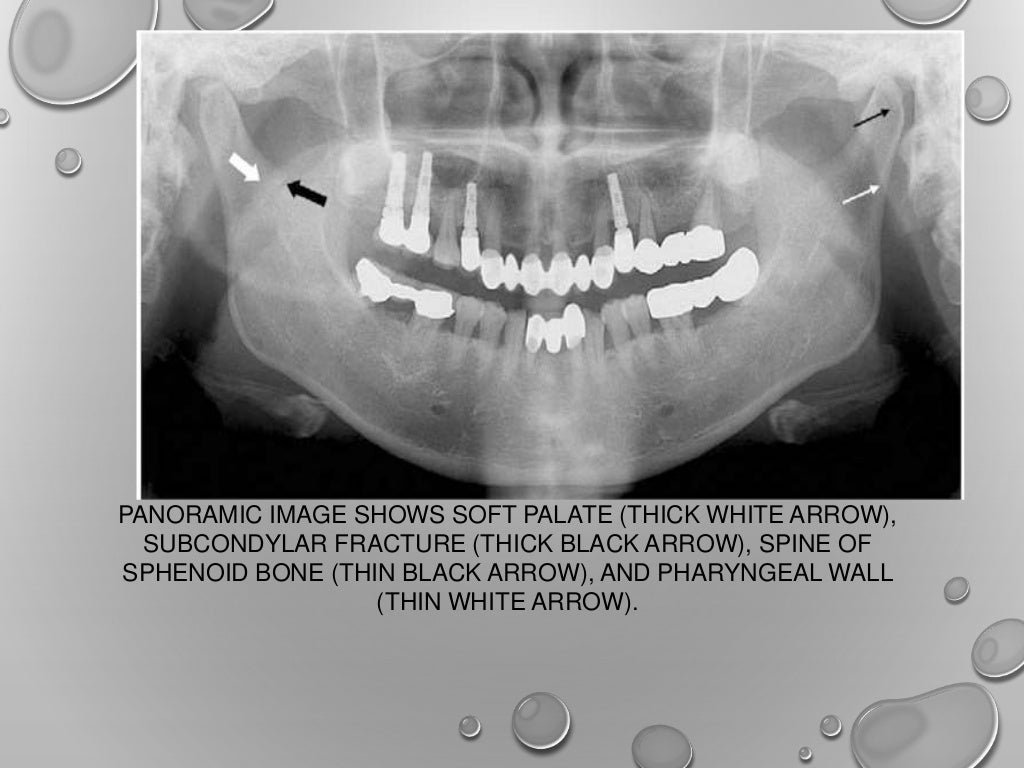

Application of opg in orthodontics Opg Dental Positioning Therefore, minor positioning errors can cause. In order to obtain diagnostically useful images, patients must be positioned carefully within the image layer or. They provide an overview of the patient’s dentition as well as surrounding. The indicator light is over tooth #9, rather than between the maxillary central incisors. This study was performed to determine the relative frequency of positioning. Opg Dental Positioning.

Application of opg in orthodontics Opg Dental Positioning In this post we will update you on the various applications of the opg, talk about observable structures when the technique is well performed, tell you how to obtain a perfect. This study was performed to determine the relative frequency of positioning errors, to identify those errors directly. They provide an overview of the patient’s dentition as well as surrounding.. Opg Dental Positioning.